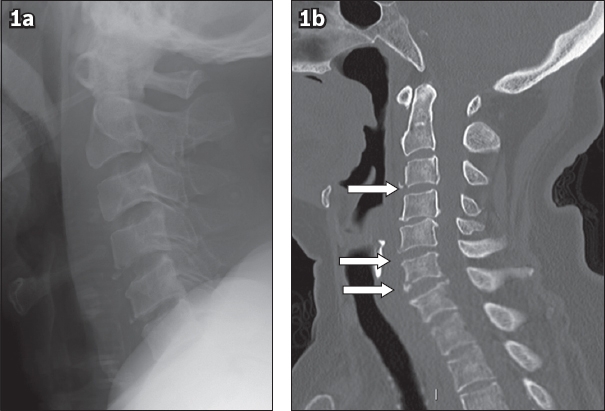

An 82-year-old woman presented to the emergency department with complaints of neck pain and bilateral upper limb paraesthesia. She had sustained mild injury to the left knee and neck after an unwitnessed fall at home the day before. Physical examination revealed tenderness over the C4–6 region but no obvious step deformity. Neurological examination of the limbs was limited by pain. Plain radiography of the cervical spine showed thickening of the pre-vertebral soft tissue and age-related degenerative changes, but no apparent fracture was seen. Subsequent computed tomography (CT) and magnetic resonance (MR) imaging were performed. What do the images (Figs.

(a) Plain lateral radiograph of the cervical spine. (b) Unenhanced sagittal CT image of the cervical spine in bone window.

Lateral radiograph of the cervical spine (

CT (